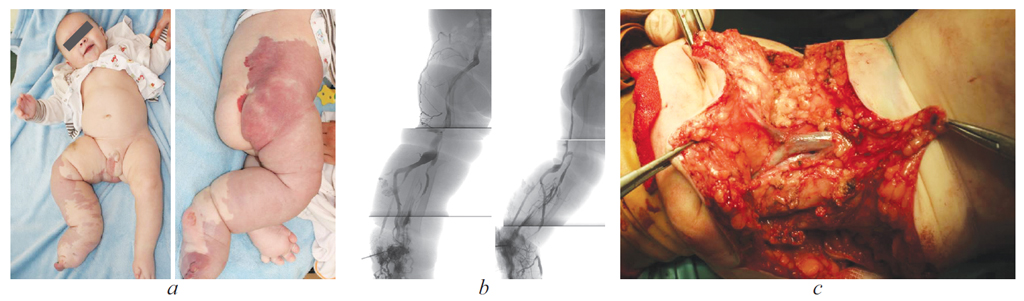

Dysplasia of the great veins (DMV) is known by the names of the authors who described this pathology as Klippel–Trenone syndrome. The clinical picture of the Klippel–Trenone syndrome in the classic description of the authors is characterized by a triad of symptoms: vascular spots, atypical varicose veins, hypertrophy of soft tissues and bones with an increase in the volume and length of the affected limb. It should be emphasized that the severity of these symptoms depends, first of all, on the type of lesion (embryonic or fetal) and the severity of the lesion. Klippel–Trenone syndrome is almost always sporadic, meaning that it develops in people with no family history of the disorder. Research shows that this condition is due to gene mutations that are not inherited. These genetic changes, called somatic mutations, occur randomly in a single cell during the early stages of development before birth. Klippel–Trenone syndrome can be caused by mutations in the PIK3CA gene. This article presents a clinical observation – the course of the disease of a 1-year-old child, with an extremely severe form of dysplasia of the great veins. In the presented clinical observation, attention is drawn to the difficulties of treating this patient against the background of the underlying chronic disease. The treatment of these patients should be carried out on the basis of a multidisciplinary hospital, which includes specialists in vascular surgery, an orthopedist and an intensive care physician. On the example of the described case, diagnostic tactics and surgical treatment are demonstrated. It is obvious that timely surgical and conservative treatment of pathology in children with dysplasia of the great veins improves the quality of life and social adaptation of children.